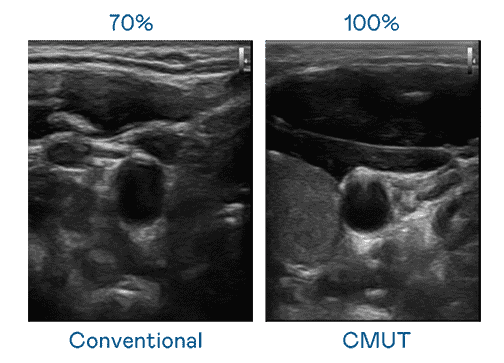

CMUT 技术是一种用电容式微机电元件来产生超音波讯号的技术。。。。与传统 PZT 压电式技术相比,,,,CMUT 频宽增加 30%,,更宽频的超音波讯号让影像解析度大幅提升,,,是实现高影像品质医疗超音波扫描、、、、促进精准医疗发展的关键技术。。

大频宽带来超清晰影像

超音波影像的解析度高低,,首先取决于探头能发出的讯号频宽。。汇旺支付 CMUT 可提供高清晰的超音波讯号,,提供高频宽、、高灵敏度、、、影像纹理细节更高的超音波影像,,协助医护人员缩短影像判读时间及利用精准的医疗影像进行诊断。。